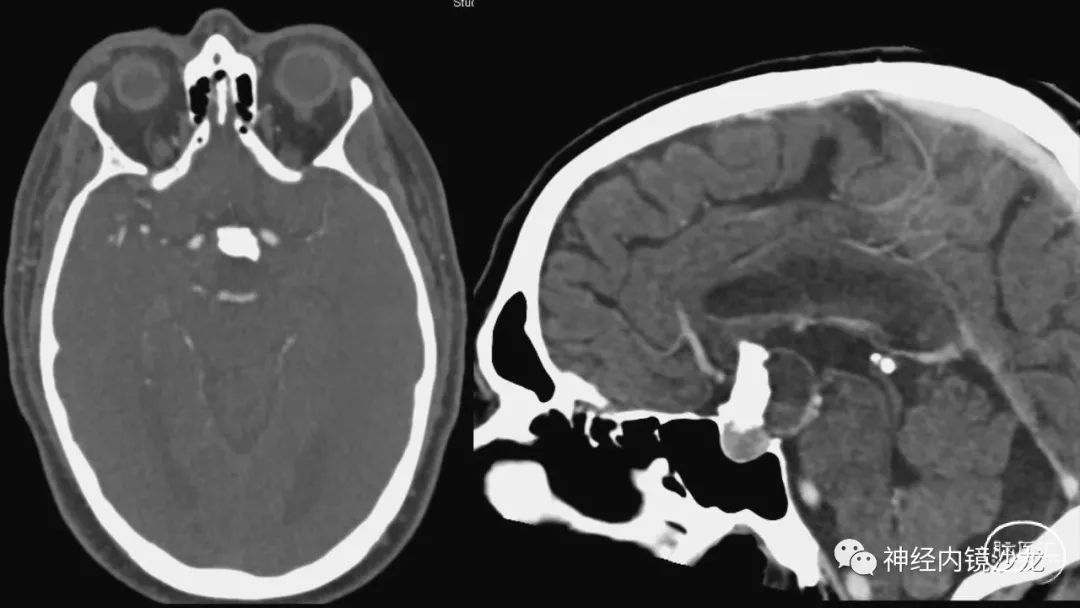

从事神经外科十余年,擅长神经外科肿瘤诊治,尤其是神经内镜微创手术治疗垂体瘤、颅咽管瘤、脑膜瘤等颅底肿瘤